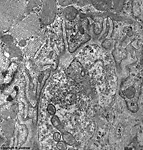

Miniaturbildübersicht neuromuskuläre Endplatte (Synapsis neuromuscularis):

motorische Endplatte A

Übersicht (Zunge, Ratte)

mot. Endplatte A

Detail 1

Eine neuromuskuläre oder motorische Endplatte = myoneurale Synapse (Terminologia histologica: Synapsis neuromuscularis, englisch: motor endplate, neuromuscular junction oder myoneural junction) stellt die Endigung einer somatomotorischen Nervenfaser zur Skelettmuskulatur dar und dient der Steuerung (Innervation) der Muskulatur. Es handelt sich also um eine spezialisierte chemische Synapse, deren flachovale, zur Muskulatur hingewandte Oberfläche ca. 4 bis zu maximal 40 µm im Durchmesser groß ist. Kommen Aktionspotentiale über das zuleitende Axon in dessen plattenartige Endauftreibung, so öffnen sich spannungsabhängige Kalziumionenkanäle. Durch den Kalziumioneneinstrom findet dann in weniger als 1 Millisekunde an der präsynaptischen Zellmembran die Exozytose acyethylcholinhaltiger Neurotransmittervesikel statt. Genauer gesagt, verschmelzen kleine Anteile der Transmittervesikelmembran mit der präsynaptischen Membran und dabei diffundiert Acytylcholin in den darunterliegenden, 20 bis 50 nm weiten, synaptischen Spalt, während gespaltener Neurotransmitter (Acetyl und Cholin) aufgenommen wird, bevor sich die Bläschenmembran durch die Anlagerung von Clathrinmolekülen wieder schließt und ins Innere des Endkolbens zurückwandert (genauere Beschreibung siehe bei Synapse). Das freigesetzte Acethylcholin bindet an die Acethylcholinrezeptoren (ca. 10.000 pro 1 µm²) der elektronendichteren post- (= sub)synaptischen Zellmembran (Plasmalemm der Muskelfaser = Sarkolemm). Dies führt zur Öffnung der Ionenkanäle der Acethylcholinrezeptoren, die durch die Zellmembran reichende Tunnelproteine sind. Dadurch kommt es zu einem extrem schnellen Natriumeinstrom und Kaliumausstrom, wobei der Natriumioneneinwärtsstrom überwiegt, was zu einer Erregung der Muskelzelle führt, wodurch sich spannungsabhängige Kalziumionenkanäle öffnen, Kalziumionen einströmen und letztlich eine Muskelkontraktion zustandekommt. Acetylcholin wird nur für 0,5 Millisekunden an seine Rezeptoren in der subsynaptischen Membran gebunden, danach wird es durch das ebenfalls an dieser Membran verankerte Enzym Acetylcholinesterase in Acetyl und Cholin gespalten. Die Spaltprodukte diffundieren in den synaptischen Spaltraum und werden, wie oben beschrieben, wieder in den synaptischen Endkolben aufgenommen.

Typischerweise finden sich in in präsynaptischen Endkolben viele kleine Mitochondrien vom Crista-Typ und bis zu 1.000.000 Neurotransmittervesikel mit durchschnittlichen Durchmessern von 50 nm, die jeweils 1.000 bis 10.000 Achetylcholin Moleküle enthalten. Zahlreiche Neurofilamente und einige Neurotubuli reichen nur ein Stück weit in die Endplatte hinein. Die der Muskulatur abgewandte Seite des Endkolbens wird von Ausläufern von Schwannschen Scheidenzellen bedeckt und damit isoliert. Der gesamte Endkolben beult sich ein Stück weit in das darunterliegende Sarkolemm ein, welches viele bis über 1 µm tiefe, parallele Falten aufweist, weshalb man von einem subneuralen Faltenfeld spricht (in den hier gezeigten Abbildungen ist dies nicht zu erkennen). Die Falten können sich auch nochmals (sekundär) verzweigen, wodurch eine enorme Oberflächenvergrößerung erfolgt. Im nur wenige Nanometer weiten Lumen der Falten findet sich glykoproteinreiches, elektronendichteres Material, welches eine Fortsetzung der Basalmembran der Muskelfaser darstellt. Typischerweise teilt sich ein somatomotorisches Axon vor seinem Ende in viele Kollateralen, die alle als motorische Endplatten enden. Da diese alle gemeinsam erregt werden, sobald ein Aktionspotential im Axon ankommt, werden sie als funktionelle (motorische) Einheit zusammengefaßt. Die Größe einer motorischen Einheit entscheidet, wieviele Skelettmuskelfasern sich gleichzeitig zusammenziehen (kontrahieren). Je differenziertere Bewegungen ein Muskel ausführt, desto kleiner sind die hier anzutreffenden motorischen Einheiten. In der Nähe der postsynaptischen Membranen finden sich in den innervierten Muskelzellen häufig beta-Glykogenkörnchen, kleine Mitochondrien vom Crista-Typ und Zellkerne. Muskelfilamente kommen erst in einiger Entfernung davon vor.